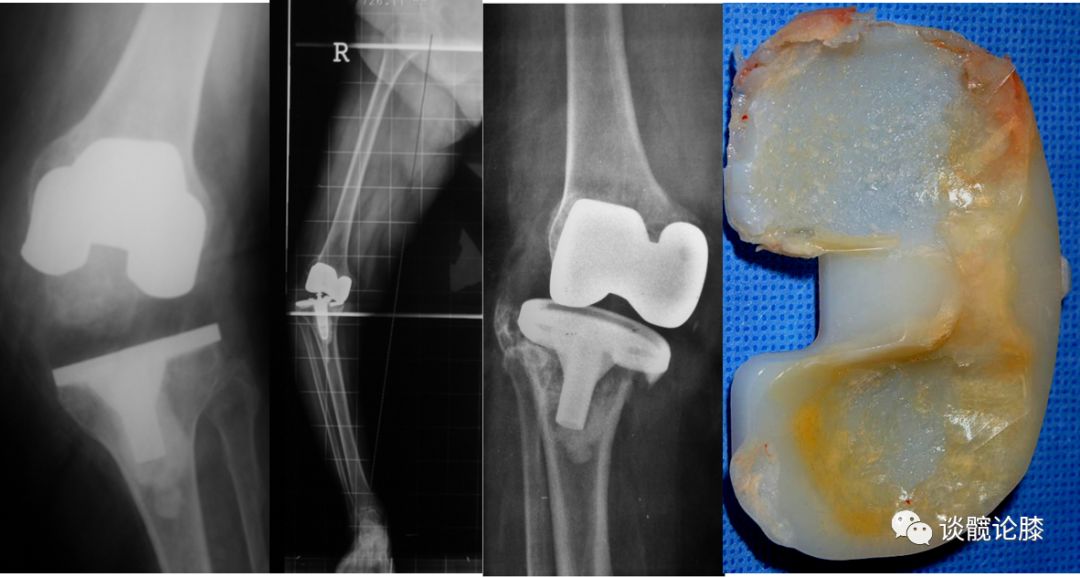

TKA术中软组织的平衡情况直接影响到术后膝关节的稳定性及功能的改善。充分良好的软组织平衡有助于减少假体松动、磨损、提高TKA的疗效。

4、聚乙烯过度磨损

4、选择合适的假体